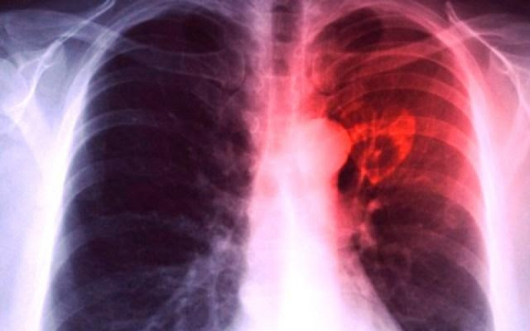

Страшно! Масово: Сервитьори болни от туберкулоза и салмонелоза!

18455 прочитаЗачестяват случаите на болни от туберкулоза, които обслужват клиенти в обекти за хранене. През последните три-четири месеца са регистрирани и служители със салмонелоза, които работят в павилиони и ресторанти, съобщи шефката на Областната дирекция по безопасност на храните във Варна, д-р Златина Димова, цитирана от "Монитор".

Тя даде пример със служителка в доста посещаван магазин за хранителни продукти, която работела, въпреки че било установено, че е болна от туберкулоза.